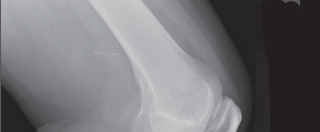

High-quality, standardized, weight-bearing radiographs are the cornerstone of preoperative planning. A standard knee series must include a weight-bearing anteroposterior (AP) view, a weight-bearing lateral view in extension, and a skyline (Merchant) view of the patella. The AP view reveals joint space narrowing, subchondral sclerosis, osteophyte formation, and the presence of subchondral cysts. The lateral view is essential for assessing patellar height (Insall-Salvati ratio) and the posterior slope of the tibia.

Crucially, we must obtain a 45-degree posteroanterior (PA) weight-bearing view (the Rosenberg view). Because cartilage wear in early-to-moderate OA predominantly affects the posterior aspect of the femoral condyles, the standard extension AP view may falsely appear normal. The flexed Rosenberg view unloads the patella and brings the worn posterior condyles into contact with the tibia, revealing hidden joint space narrowing. Furthermore, a full-length, hip-to-ankle standing radiograph is highly recommended, particularly in patients with severe deformities or a history of prior femoral/tibial fractures, to accurately determine the mechanical axis and identify any extra-articular deformities that might complicate intramedullary instrumentation.